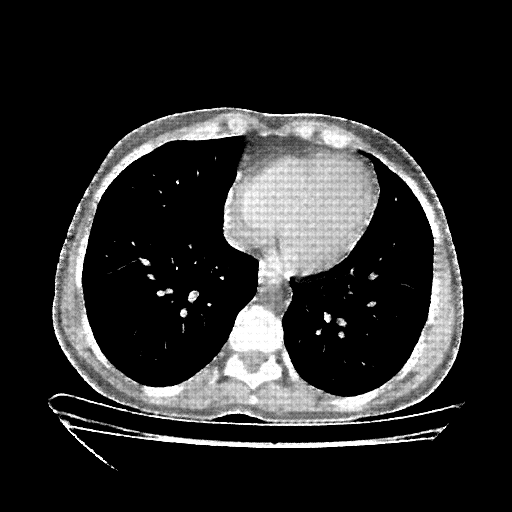

Original NATIVE CT scan (input)

Full window (WL 1023.5, WW 4095 β†’ Low βˆ’1024, High +3071)

Reconstructed NATIVE CT scan (cycle consistency)

Original VENOUS CT scan

Generated VENOUS CT scan (A→B translation)